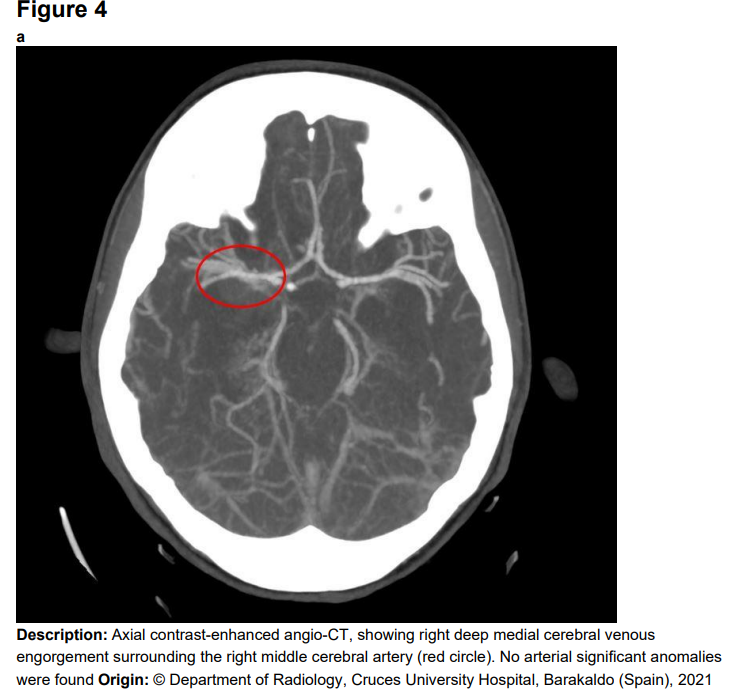

分析蛛网膜下腔出血真没那么简单

图片尺寸1000x569